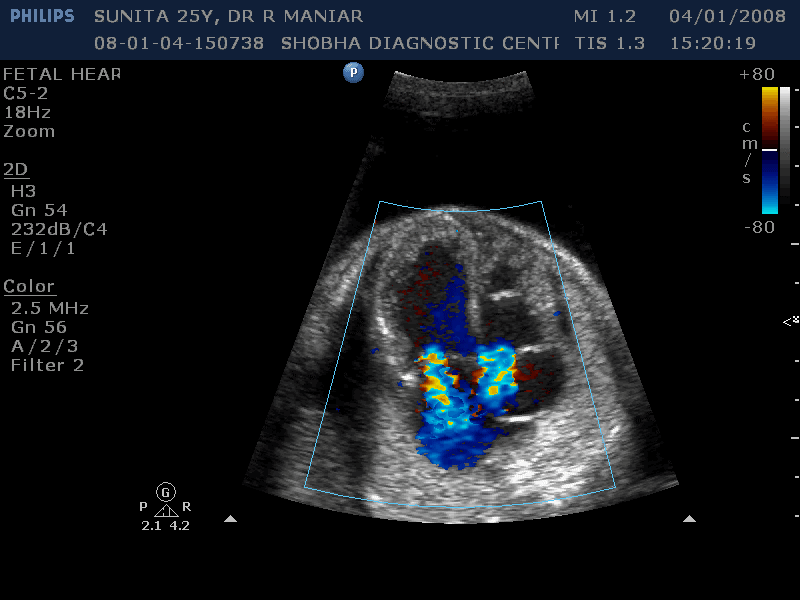

Fetal Echocardiography

WE ROUTINELY DO FETAL ECHOCARDIGRAPHY AT OUR CENTRE